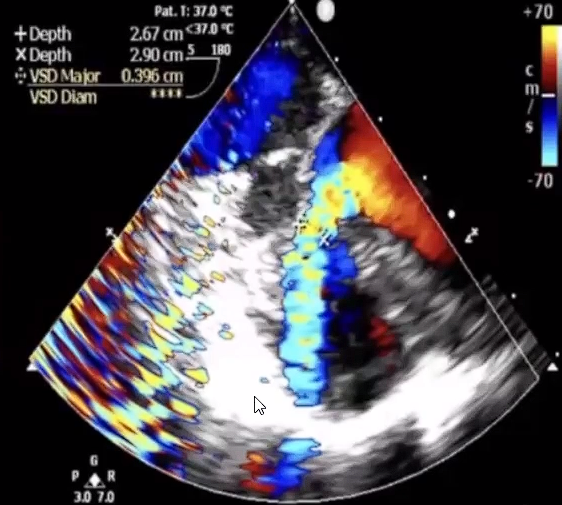

该例手术患者是4岁男性患儿,术前经胸超声检查示室间隔缺损4mm,室水平左向右高速分流。术者团队综合评估后,决定使用全降解封堵器行室间隔缺损的封堵。

▲术前超声